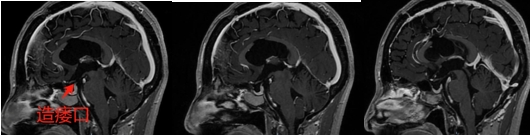

诊治过程:结合患者临床表现及影像学表现,初步诊断考虑为三脑室后部胶质瘤合并梗阻性脑积水可能性大,术前制定的手术方案为经胼胝体穹隆间入路三脑室后部肿瘤切除术+脑室镜辅助下三脑室底造瘘术,该手术方式既可切除肿瘤获取病理,同时可行三脑室底造瘘解决脑积水症状。术中采用冠状缝前额部弧形切口,术中沿纵裂牵开双侧大脑半球,探及胼胝体,沿中线切开胼胝体,分离双侧透明隔,暴露双侧穹隆,严格沿中线分离双侧穹隆,保护两侧穹隆的完整,避免引起术后的记忆力障碍,牵拉开双侧穹隆,进入中间帆,显露并分离双侧大脑内静脉继续向下,经脉络膜隔进入三脑室,完全显露肿瘤组织,肿瘤组织呈灰红色,血供极其丰富,与中脑黏连紧密,仔细分离,分块全切肿瘤,双侧大脑内静脉及中脑保护良好,中脑导水管通畅。肿瘤完全切除后,考虑到术后局部粘连、肿瘤复发等因素可能导致脑积水不缓解,置入脑室镜向前方探查,小心切开中间块,在双侧乳头体与漏斗隐窝之间,行三脑室底部造瘘并打开Liliequist膜及基底动脉旁蛛网膜,确认漏口通畅且与脚间池相通。患者术后恢复过程平稳,颅脑MRI提示肿瘤切除满意,脑积水缓解。术后病理结果示:中枢神经细胞瘤(2级)。术后予以放疗GTV 5400cGy、PTV 5040cGy,28f。现术后已3年,复查未见肿瘤复发,脑积水已完全缓解。